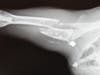

Bullet Lodged in Cat's Shoulder

An x-ray found that Rubi had been shot in her upper right leg. The bullet passed through her leg, breaking it in half, and then lodged in her shoulder.

Tiffany Rimar, DVM, performed surgery on Rubi and left the bullet in Rubi's shoulder because trying to remove it could have damaged the cat's leg even more. Her leg was so severely damaged that amputation was a possibility.